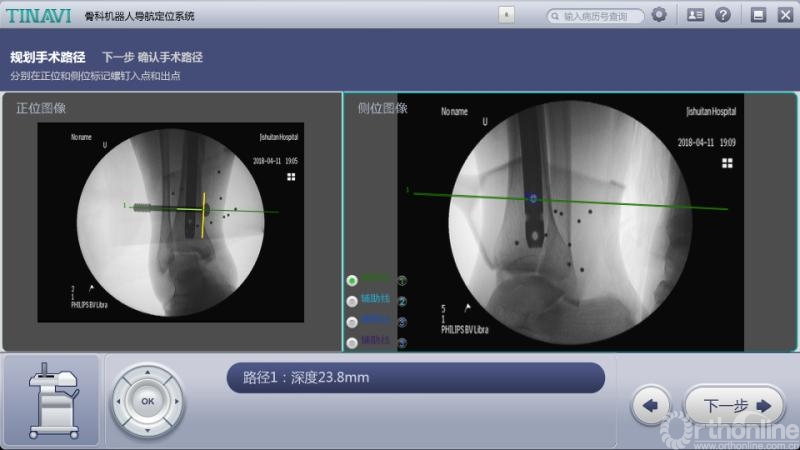

2018年4月11日深夜11点,积水潭医院手术室内依然灯明如昼,在骨科导航机器人的“帮助”下,两台足踝外科手术正有条不紊地进行着。随着最后一颗螺钉的精准置入,透视显示,螺钉位置与术前规划一致,手术非常成功!

传统手术方法需要大面积暴露患部,导针反复操作确定位置、同时多次透视,手术时间长、患者损伤大,并发症几率高。而现在只需要把融合的关节面进行处理后,安装好骨科导航机器人,把伤口用敷料盖好后,在病人体外用机器人做规划,并按照规划精准置入螺钉。病人真正的手术时间大大缩短,暴露的伤口小、辐射少、手术效果达到最佳。

术中规划螺钉位置

术中规划后踝螺钉位置